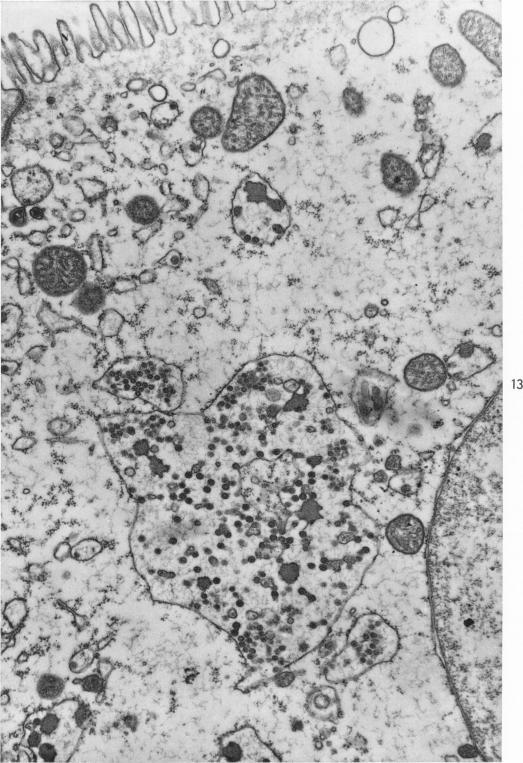

Electron-Microscopic Study of the Intestinal Epithelium of Mice Infected with the Agent of Epizootic Diarrhea of Infant Mice (EDIM Virus).

Am J Pathol. 1967 Jul;51(1):39-60.